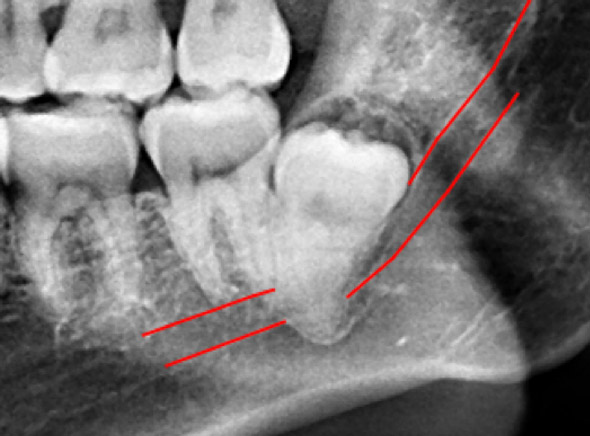

(兩條紅線中間黑色區域即為神經管)

外面拔時易斷裂於骨頭內而難以取出